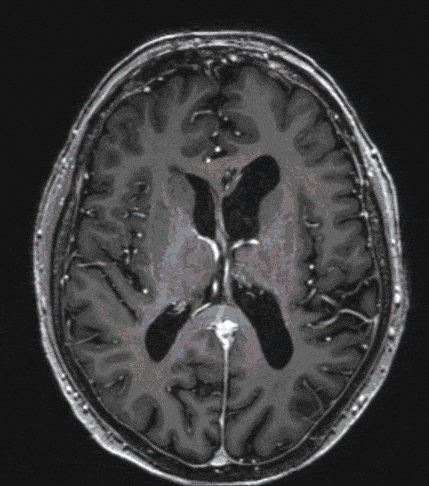

Pituitary tumors are usually benign tumors of the pituitary gland (hypophysis), which, if large enough, can lead primarily to visual disturbances and/or hormonal disturbances. Interdisciplinary treatment, both before and after surgery, is therefore crucial for the outcome.

The therapy of choice, if the tumor reaches a certain size and symptoms are present, is surgical removal (the exception is prolactinoma).